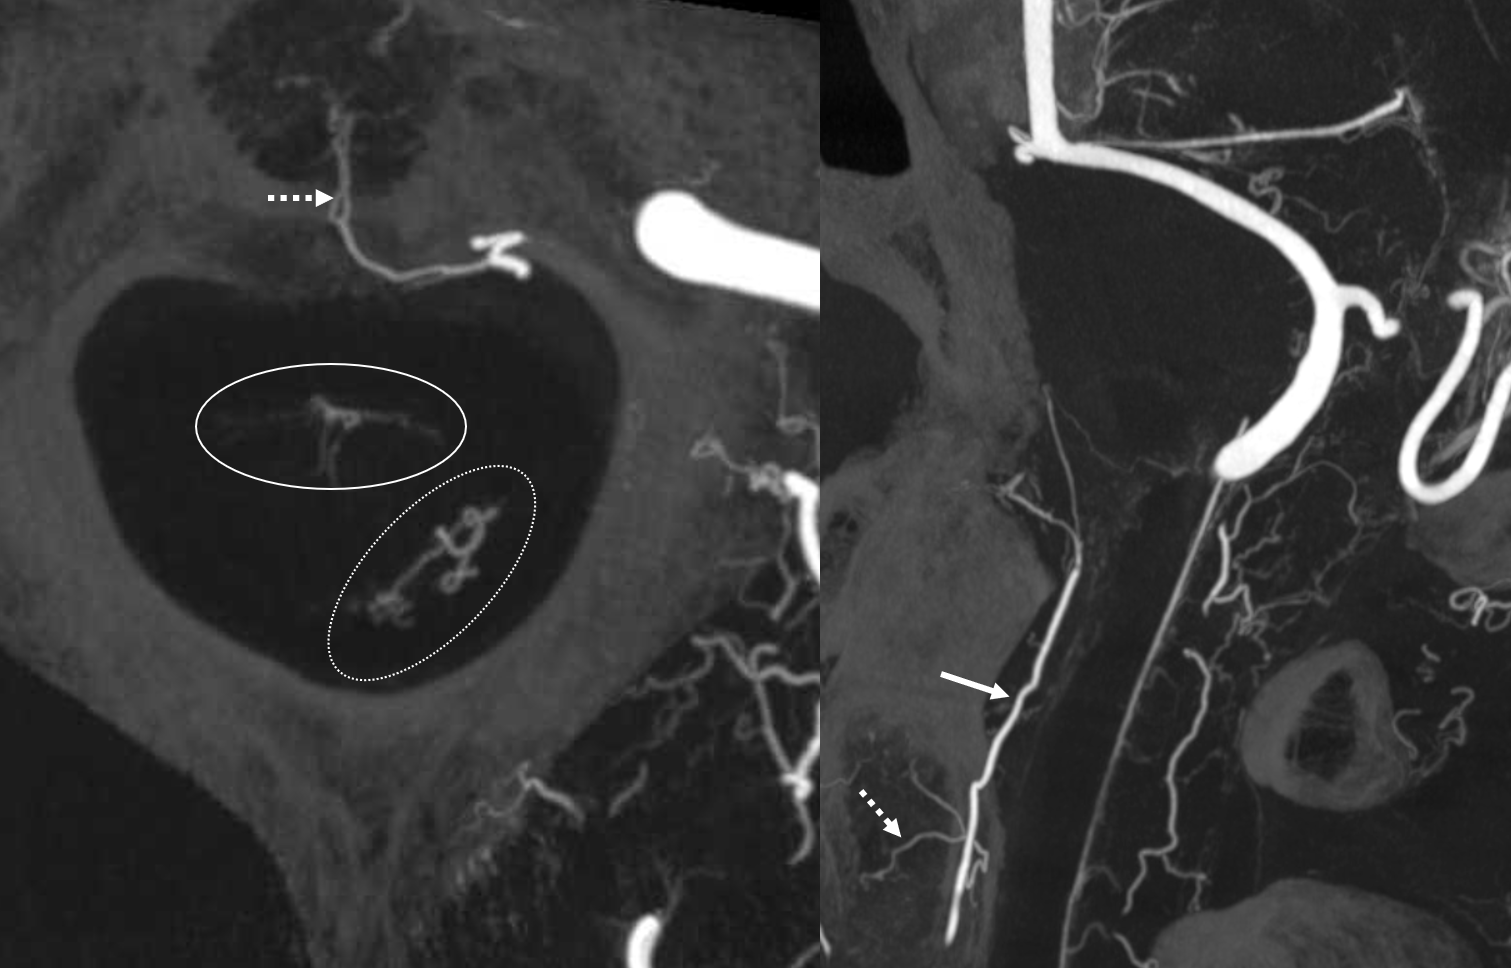

Another case — cone beam CT is great of course for odontoid arcade and most everything else. Left vert injection opacifies the odontoid arcade (arrows) and its supply to C2 bone (dashed arrows). Note also excellent visualization of both anterior spinal artery territory (white oval) and very prominent posterior / lateral spinal region (dashed white oval)

The same case, now with microcatheter position in the odontoid arcade. The same supply to the bone is noted, however note complete lack of spinal cord or radicular artery visualization. Direct spinal cord supply from the odontoid arcade is exceptionally rare, making it a relatively good embolization position in what is still a very treacherous area.